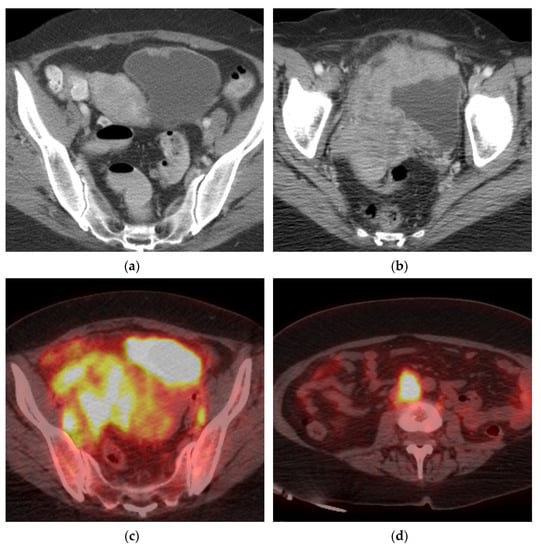

FDG PET/CT is of limited use in evaluating the urinary collecting system due to urinary excretion of FDG, but useful in evaluating for distant metastases (Figure 7) [32]. One systematic review and meta-analysis found a pooled sensitivity of 0.82 and pooled specificity of 0.89 for metastatic lesions [33]. FDG PET/CT changed management in 18–68% of patients compared to conventional CT [22]. A recent consensus statement by the European Association of Urology (EAU) and the European Society for Medical Oncology (ESMO) states that FDG PET/CT should be included in the staging of oligometastatic disease when considering radical treatment to minimize the risk of overtreatment [34]. NCCN also suggests FDG PET/CT may be beneficial in select patients with T2 and may change management in ≥cT3 disease [35]. The benefit of FDG PET/CT in lymph node staging is limited. One meta-analysis showed a pooled sensitivity of 57% and specificity of 92% for initial pelvic lymph node staging. In a prospective study of 61 patients undergoing FDG PET/CT prior to radical cystectomy and extended pelvic lymph node dissection, FDG PET/CT did not improve diagnostic accuracy for detecting lymph node metastases compared to conventional CT [36].

Figure 7.

Marked progression of locally advanced bladder cancer and metastatic disease. (a) Axial CT image demonstrates a small lesion in the anterior bladder which went untreated for 16 months. (b) Follow up axial CT image showing significant progression of the mass which now extends beyond the bladder to involve the uterus, right adnexa, and right pelvic side wall. (c) Axial PET/CT image redemonstrating the locally advanced mass with bilateral pelvic lymphadenopathy. (d) Axial PET/CT image shows metastatic retroperitoneal lymphadenopathy. (e) Coronal PET/CT image also showing metastatic left supraclavicular lymphadenopathy. Biopsy of the left supraclavicular node showed poorly differentiated carcinoma compatible with bladder primary.